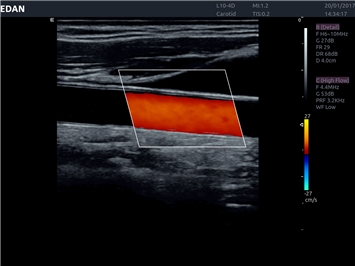

• Тканевая допплеровская визуализация (TDI)

• Сосудистой диагностики

Цветовой допплер:

Да

Энергетический допплер: